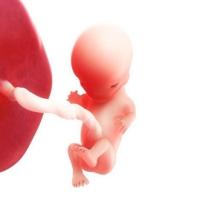

Dalla 9° alla 11° settimana: finisce il periodo embrionale ed inizia quello fetale. Gli occhi si chiudono, l’ernia addominale rientra e le cellule del sangue iniziano a essere prodotte dal fegato;

12° settimana: si differenziano i genitali esterni ed iniziano i primi movimenti fetali data l’acquisizione del tono muscolare. La milza e non più il fegato produce le cellule del sangue.